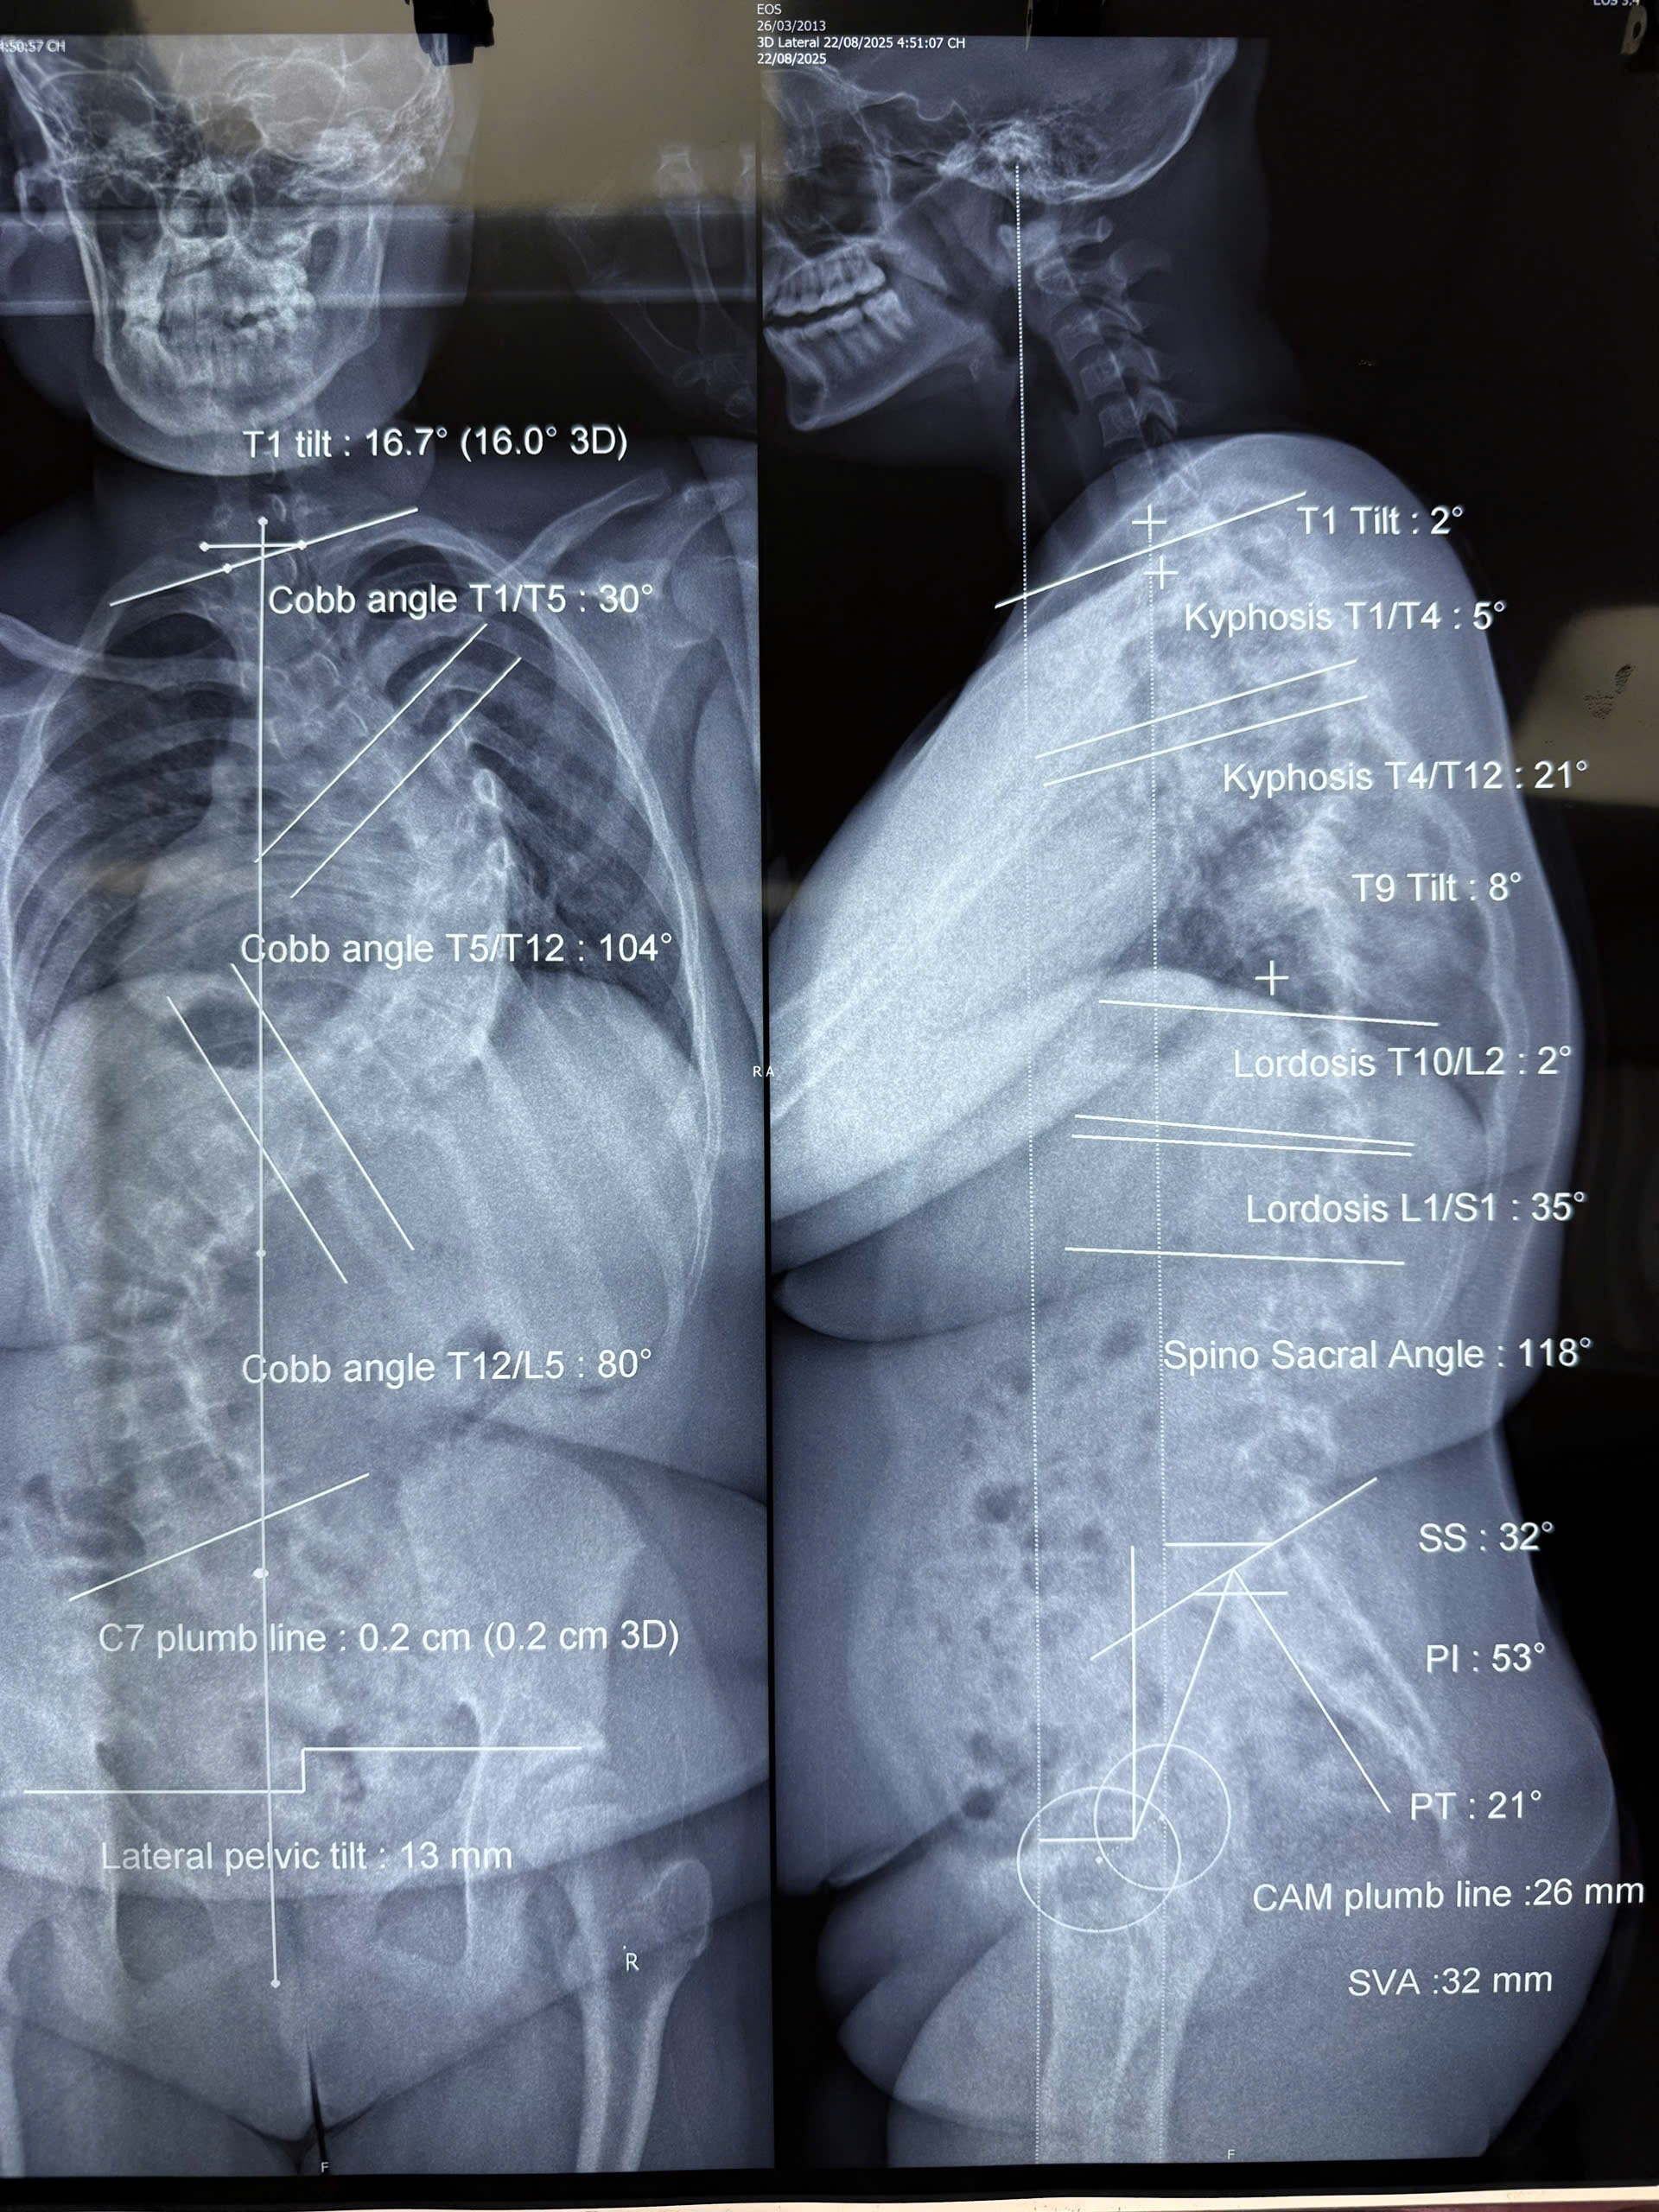

Chỉ trong 7 tháng chờ đợi phẫu thuật, độ vẹo của L. tăng nhanh từ 78 độ lên 104 độ, kéo theo đường cong thứ hai 80 độ ở vùng thắt lưng. Trước mổ, bé không thể nằm thẳng và thường xuyên gặp các bệnh lý về hô hấp.

Độ vẹo của bé L. tiến triển nhanh, từ 78 lên 104 độ chỉ trong vòng 7 tháng. Ảnh: BVCC.